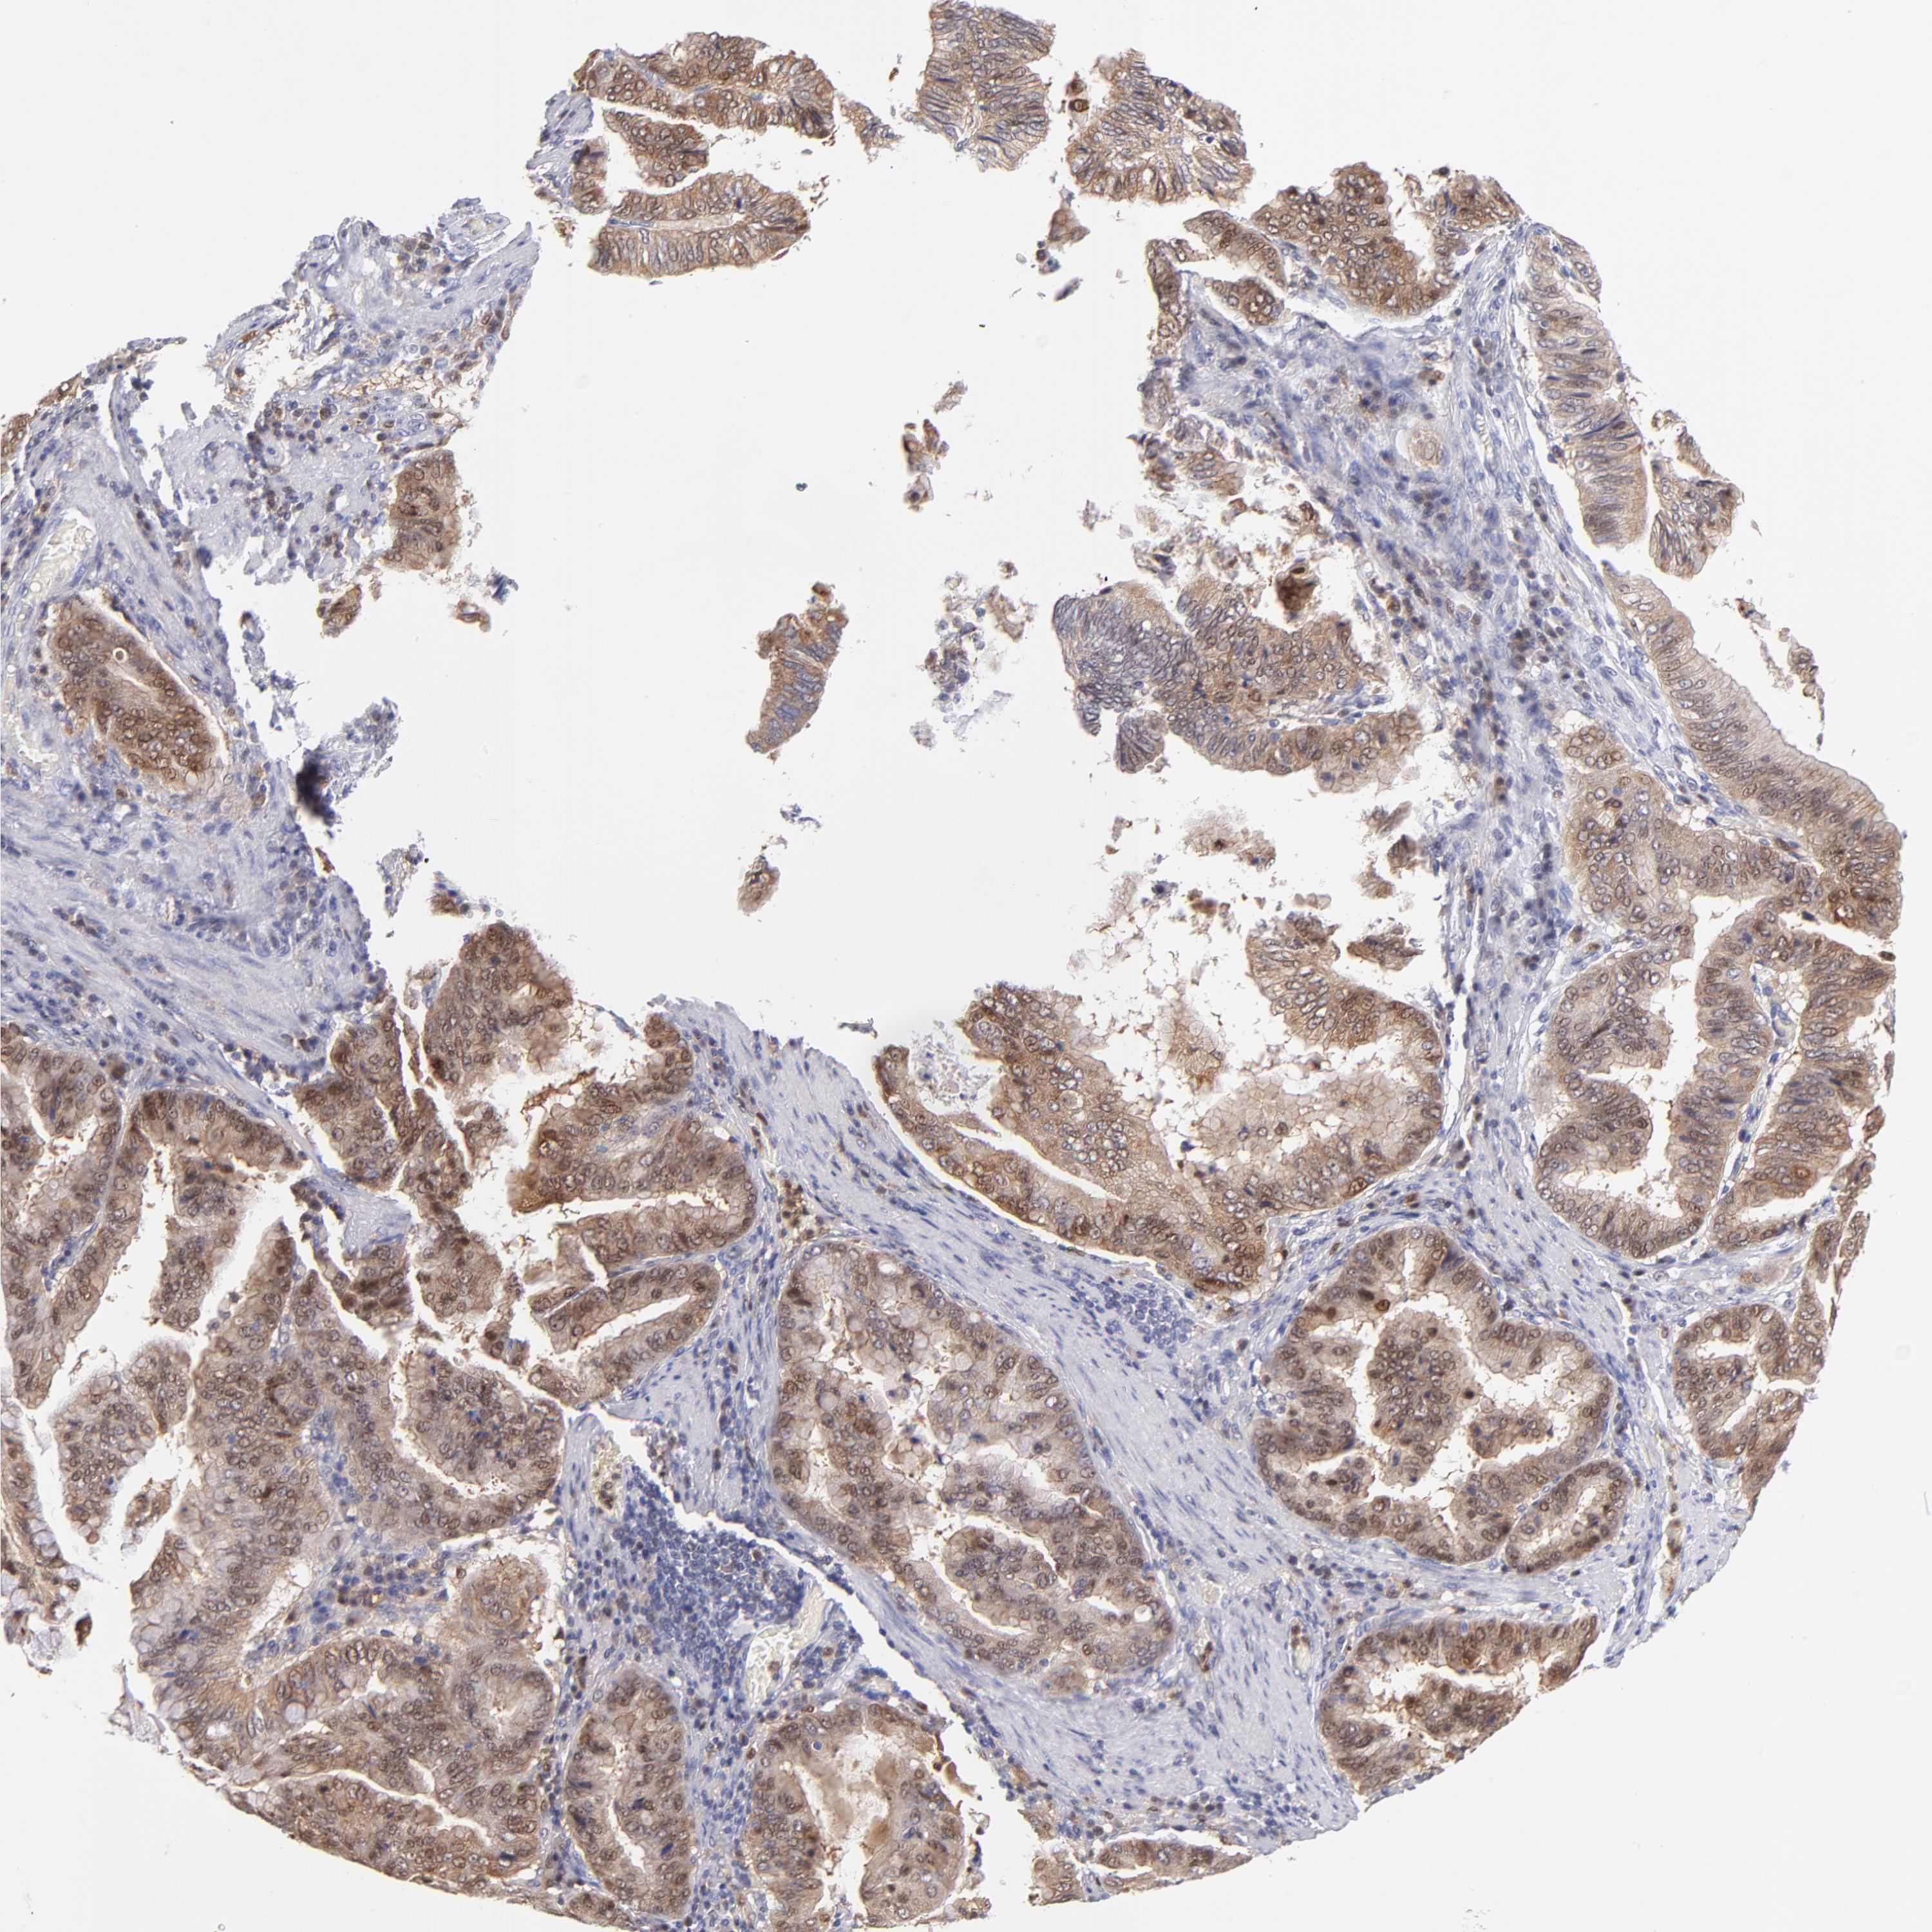

STOMACH CANCER - Protein expressioni

A mouse-over function shows sample information and annotation data. Click on an image to view it in a full screen mode. Samples can be filtered based on level of antibody staining by selecting one or several of the following categories: high, medium, low and not detected. The assay and annotation is described here.

Antibody stainingi

Antibody staining in the annotated cell types in the current human tissue is reported as not detected, low, medium, or high, based on conventional immunohistochemistry profiling in selected tissues. This score is based on the combination of the staining intensity and fraction of stained cells.

Each image is clickable and will lead to virtual microscopy that enables deeper exploration of all samples and also displays staining intensity scores, fraction scores and subcellular localization as well as patient and tissue information for each sample.

Antibody HPA000722

Antibody CAB003771

Staining

High

Medium

Low

Not detected

Intensity

Strong

Moderate

Weak

Negative

Quantity

>75%

75%-25%

<25%

None

Location

Nuclear

Cytoplasmic/membranous

Cytoplasmic/membranous,nuclear

Adenocarcinoma, NOS